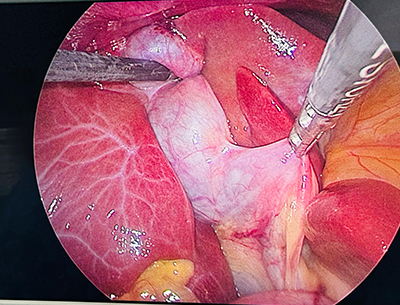

Dr Monika Joshi presented in the session on “Horrors of Laparoscopy” at the prestigious Indian Association of Gastrointestinal Endo-Surgeons (IAGES) ELSA – an international conference held at the elegant The Westin Mumbai Powai Lake.

Presenting on one of the most challenging and feared complications in minimally invasive surgery was both humbling and enriching. The session brought together experienced surgeons from across the globe, fostering meaningful discussions, shared learning, and surgical wisdom.